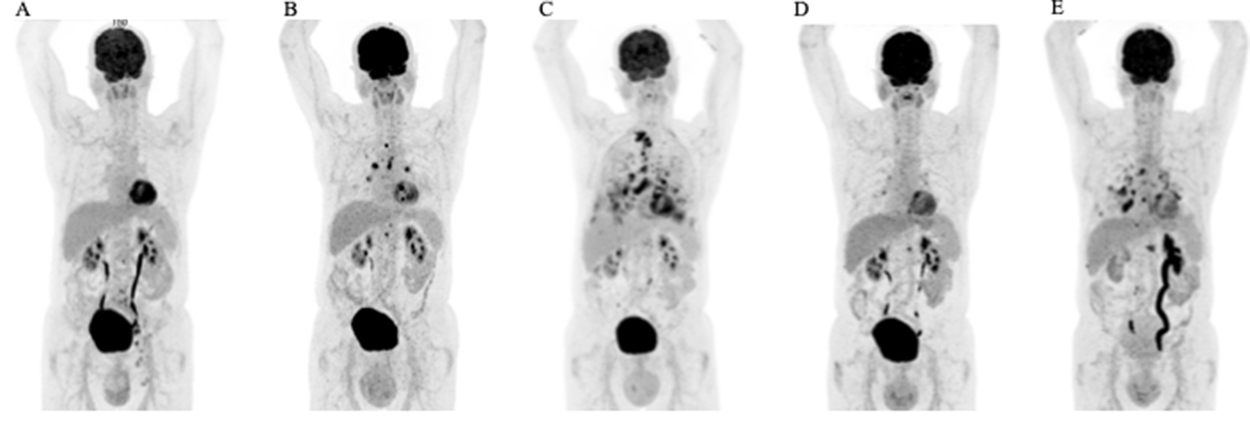

Figure 2: Therapeutic efficacy assessed by FDG-PET/CT scans. Coronal maximum intensity projection images (A) at the initial presentation, (B) following recurrent disease after radiation therapy (C) after lapatinib treatment (D) best response during trastuzumab and carboplatin treatment, and (E) disease progression after 10 cycles of trastuzumab and carboplatin.

We report on an 80-year-old patient in excellent general condition (ECOG 0), who was referred to our clinic for further treatment of a chronic scrotal eczema. Upon physical examination, erythematous plaque with multiple nodules affecting the skin of the scrotum was seen, along with prominent inguinal lymphadenopathy (Figure 1A). Histologic analysis showed an ulcerated and invasive adenocarcinoma with Paget cells, consistent with the diagnosis of extramammary Paget’s disease. Furthermore, enlarged and metabolic active inguinal, iliacal and interaortocaval lymph-nodes were detectable on PET/CT-imaging (Figure 2A). Indeed, fine needle aspiration (FNA) confirmed the presence of lymph node metastasis. Fluorescence in situ (FISH) for HER2 amplification was negative and immune-histochemical staining for HER2 was 2+, classifying the patient as HER2 negative, according to current ASCO/CAP Guidelines [1]. Urological and gastroenterological examination did not reveal underlying malignancy of the prostate or gastrointestinal tract, respectively. After interdisciplinary discussion, the patient was opted for radiotherapy of the penoscrotal region and metabolic active lymph nodes (cumulative 60Gy), which was well tolerated.

6 months into follow-up, scrotal inflammation re-occurred (Figure 1B). Multiple mapping skin biopsies revealed apocrine adenocarcinoma in situ. PET/CT imaging showed new metabolic activity of the thoracal and retrocrural lymph-nodes, and a metabolically active nodulous in the superior right lobe of the lung (Figure 2B). FNA of the pulmonal nodule confirmed the presence of pulmonary metastasis. In order to identify targetable molecular alterations, next-generation sequencing (Oncomine Focus Assay) of the scrotal tumor was performed, revealing an activating ERBB2S310F point mutation. Accordingly lapatinib treatment (1250mg daily) was initiated [2]. However, the patient’s general condition deteriorated continuously along with respiratory insufficiency, leading to the necessity of continuous oxygen supplementation. While scrotal inflammation worsened, PET/CT imaging showed disease progression with pleural effusions and bone metastasis (Figure 1C and 2C, respectively). Again, histological analysis of FDG-avid bronchial mucosa was performed, confirming the presence of Paget-cells. Interestingly, HER2 immune-histochemical staining was strongly positive (3+) classifying the patient as HER2 positive. Therefore, lapatinib was discontinued and the patient was treated with trastuzumab (6mg/kg body weight) and carboplatin (300mg) every 3 weeks. Within one month, the patient’s general condition improved rapidly and oxygen supplementation was not further needed. In addition, scrotal inflammation resolved (Figure 1D). PET/CT imaging showed partial response of all lymph node metastasis, as well as subtotal response of pulmonary and bone metastasis (Figure 2D). A single bone metastasis at the cervical vertebra was irradiated due to local disease progression.

After 10 cycles of trastuzumab and carboplatin, follow-up PET/CT imaging displayed disease progression, with re-occurrence of multiple lymph-node and pulmonary metastasis (Figure 2E). Scrotal inflammation was mildly increased (Figure 1E). Molecular analysis (Oncomine Focus Assay) from a newly developing and metabolic active hilar lymph node metastasis was performed. Apart from the known ERBB2S310F mutation, additional genomic alterations were identified, including ERBB3A232V and PIK3CAG106V point mutations, and amplification of CDK6. In order to identify further potential treatable targets, Foundation One analysis was performed, revealing additional, equivocal MET amplification. Given the fact, that ERRB3 mutations have been associated with resistance to ERBB2 targeted treatment strategies, trastuzumab / carboplatin was discontinued and afatinib, an ERRB family Inhibitor, was initiated [3]. Unfortunately, 8 days after initiation of afatinib, the patient died of community acquired pneumonia.